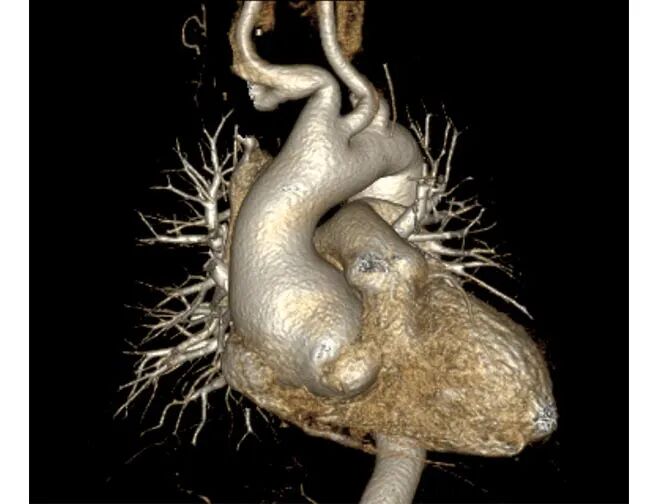

Bentall术前主动脉CTA 例1

Bentall术前主动脉CTA 例2